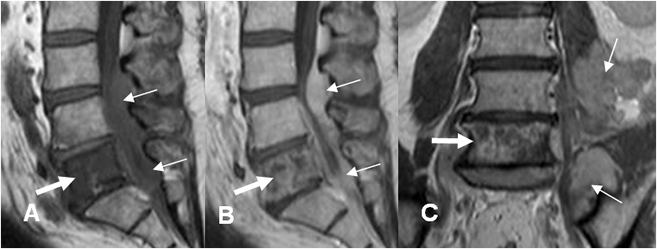

Fig 186. Linfoma.

A: TAC axial, B: RM sagital en T1 con contraste y C: RM sagital en T2. Cúmulo de adenopatías paravertebrales dorsales, con compromiso vertebral y masa de tejidos blandos que se extiende al canal modular. (Flecha).